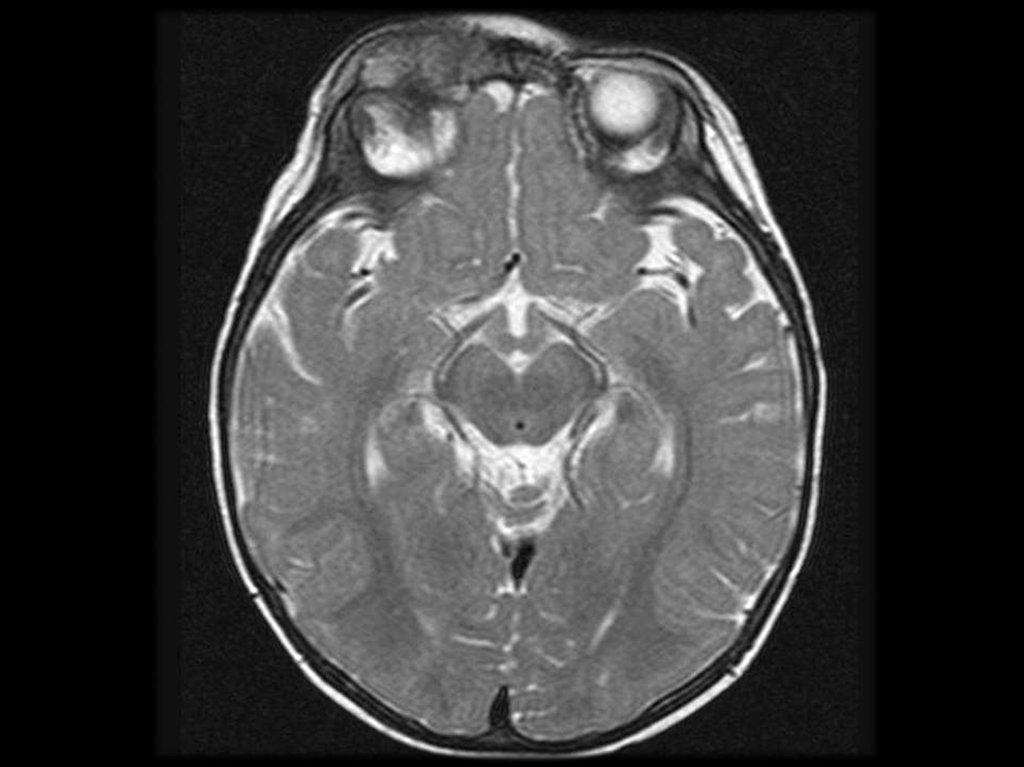

Поражение ц.н.с. (50 – 60%).

Наиболее часты невриты по типу последовательного

поражения многих нервов. При этом двигательные

расстройства

(слабость,

отсутствие

рефлексов,

дистальные парезы и параличи) преобладают над

сенсорными

(боль,

парестезии,

снижение

чувствительности).

Поражение сосудов головного мозга протекает по

типу очагового поражения различной локализации

или с клиникой менингоэнцефалита.